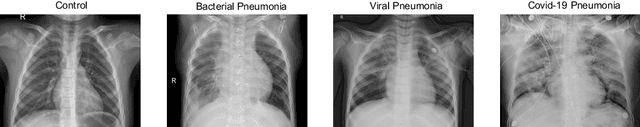

Abstract:The ongoing crisis of the COVID-19 (Coronavirus disease 2019) pandemic has changed the world. According to the World Health Organization (WHO), 4 million people have died due to this disease, whereas there have been more than 180 million confirmed cases of COVID-19. The collapse of the health system in many countries has demonstrated the need of developing tools to automatize the diagnosis of the disease from medical imaging. Previous studies have used deep learning for this purpose. However, the performance of this alternative highly depends on the size of the dataset employed for training the algorithm. In this work, we propose a classification framework based on sparse coding in order to identify the pneumonia patterns associated with different pathologies. Specifically, each chest X-ray (CXR) image is partitioned into different tiles. The most relevant features extracted from PCA are then used to build the dictionary within the sparse coding procedure. Once images are transformed and reconstructed from the elements of the dictionary, classification is performed from the reconstruction errors of individual patches associated with each image. Performance is evaluated in a real scenario where simultaneously differentiation between four different pathologies: control vs bacterial pneumonia vs viral pneumonia vs COVID-19. The accuracy when identifying the presence of pneumonia is 93.85%, whereas 88.11% is obtained in the 4-class classification context. The excellent results and the pioneering use of sparse coding in this scenario evidence the applicability of this approach as an aid for clinicians in a real-world environment.